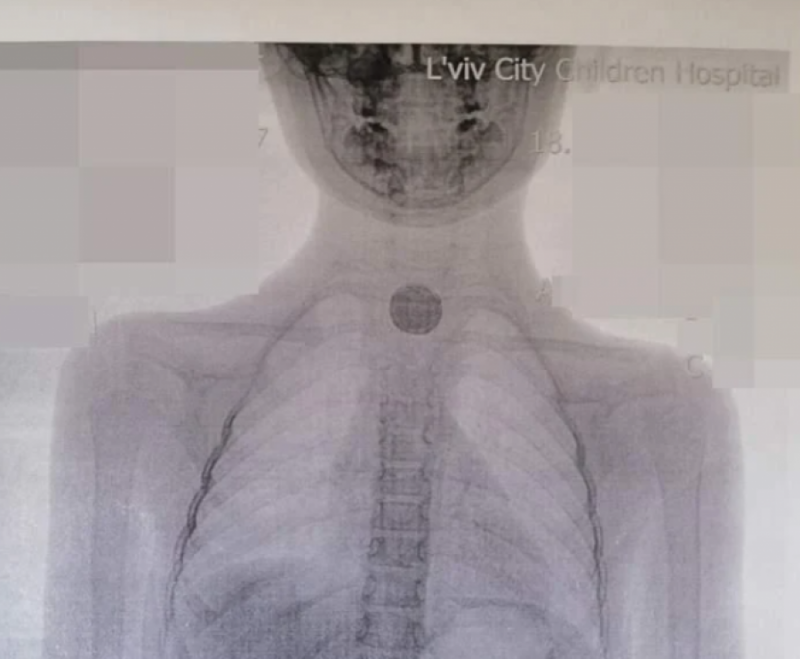

"Все чорне і обпалене": у Львові дівчинка проковтнула батарейку і сильно пошкодила стравохід

12 липня 2021, 20:51

Україна